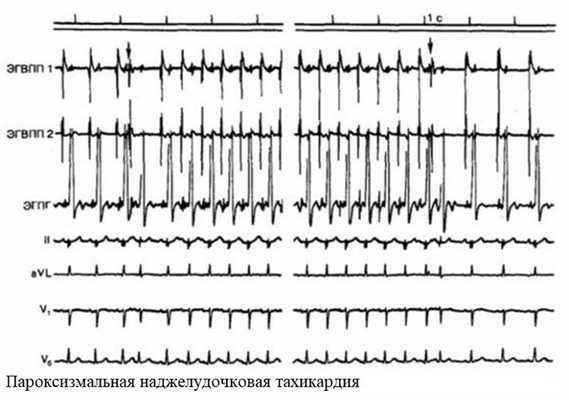

Пароксизмальная тахикардия

Пароксизмальные состояния редко возникают во время беременности без предшествующего фона. Обычно они осложняют ишемию миокарда. По локализации могут быть предсердными и желудочковыми.

Приступ пароксизмальной тахикардии возникает внезапно. Учащается сердцебиение до 200 уд./мин. Могут быть жалобы на шум в ушах, головокружение. У беременных приступ часто протекает на фоне тошноты. Возможно обратимое нарушение речи.

Длительный приступ пароксизмальной тахикардии опасен для матери и плода. Не исключено прерывание беременности.